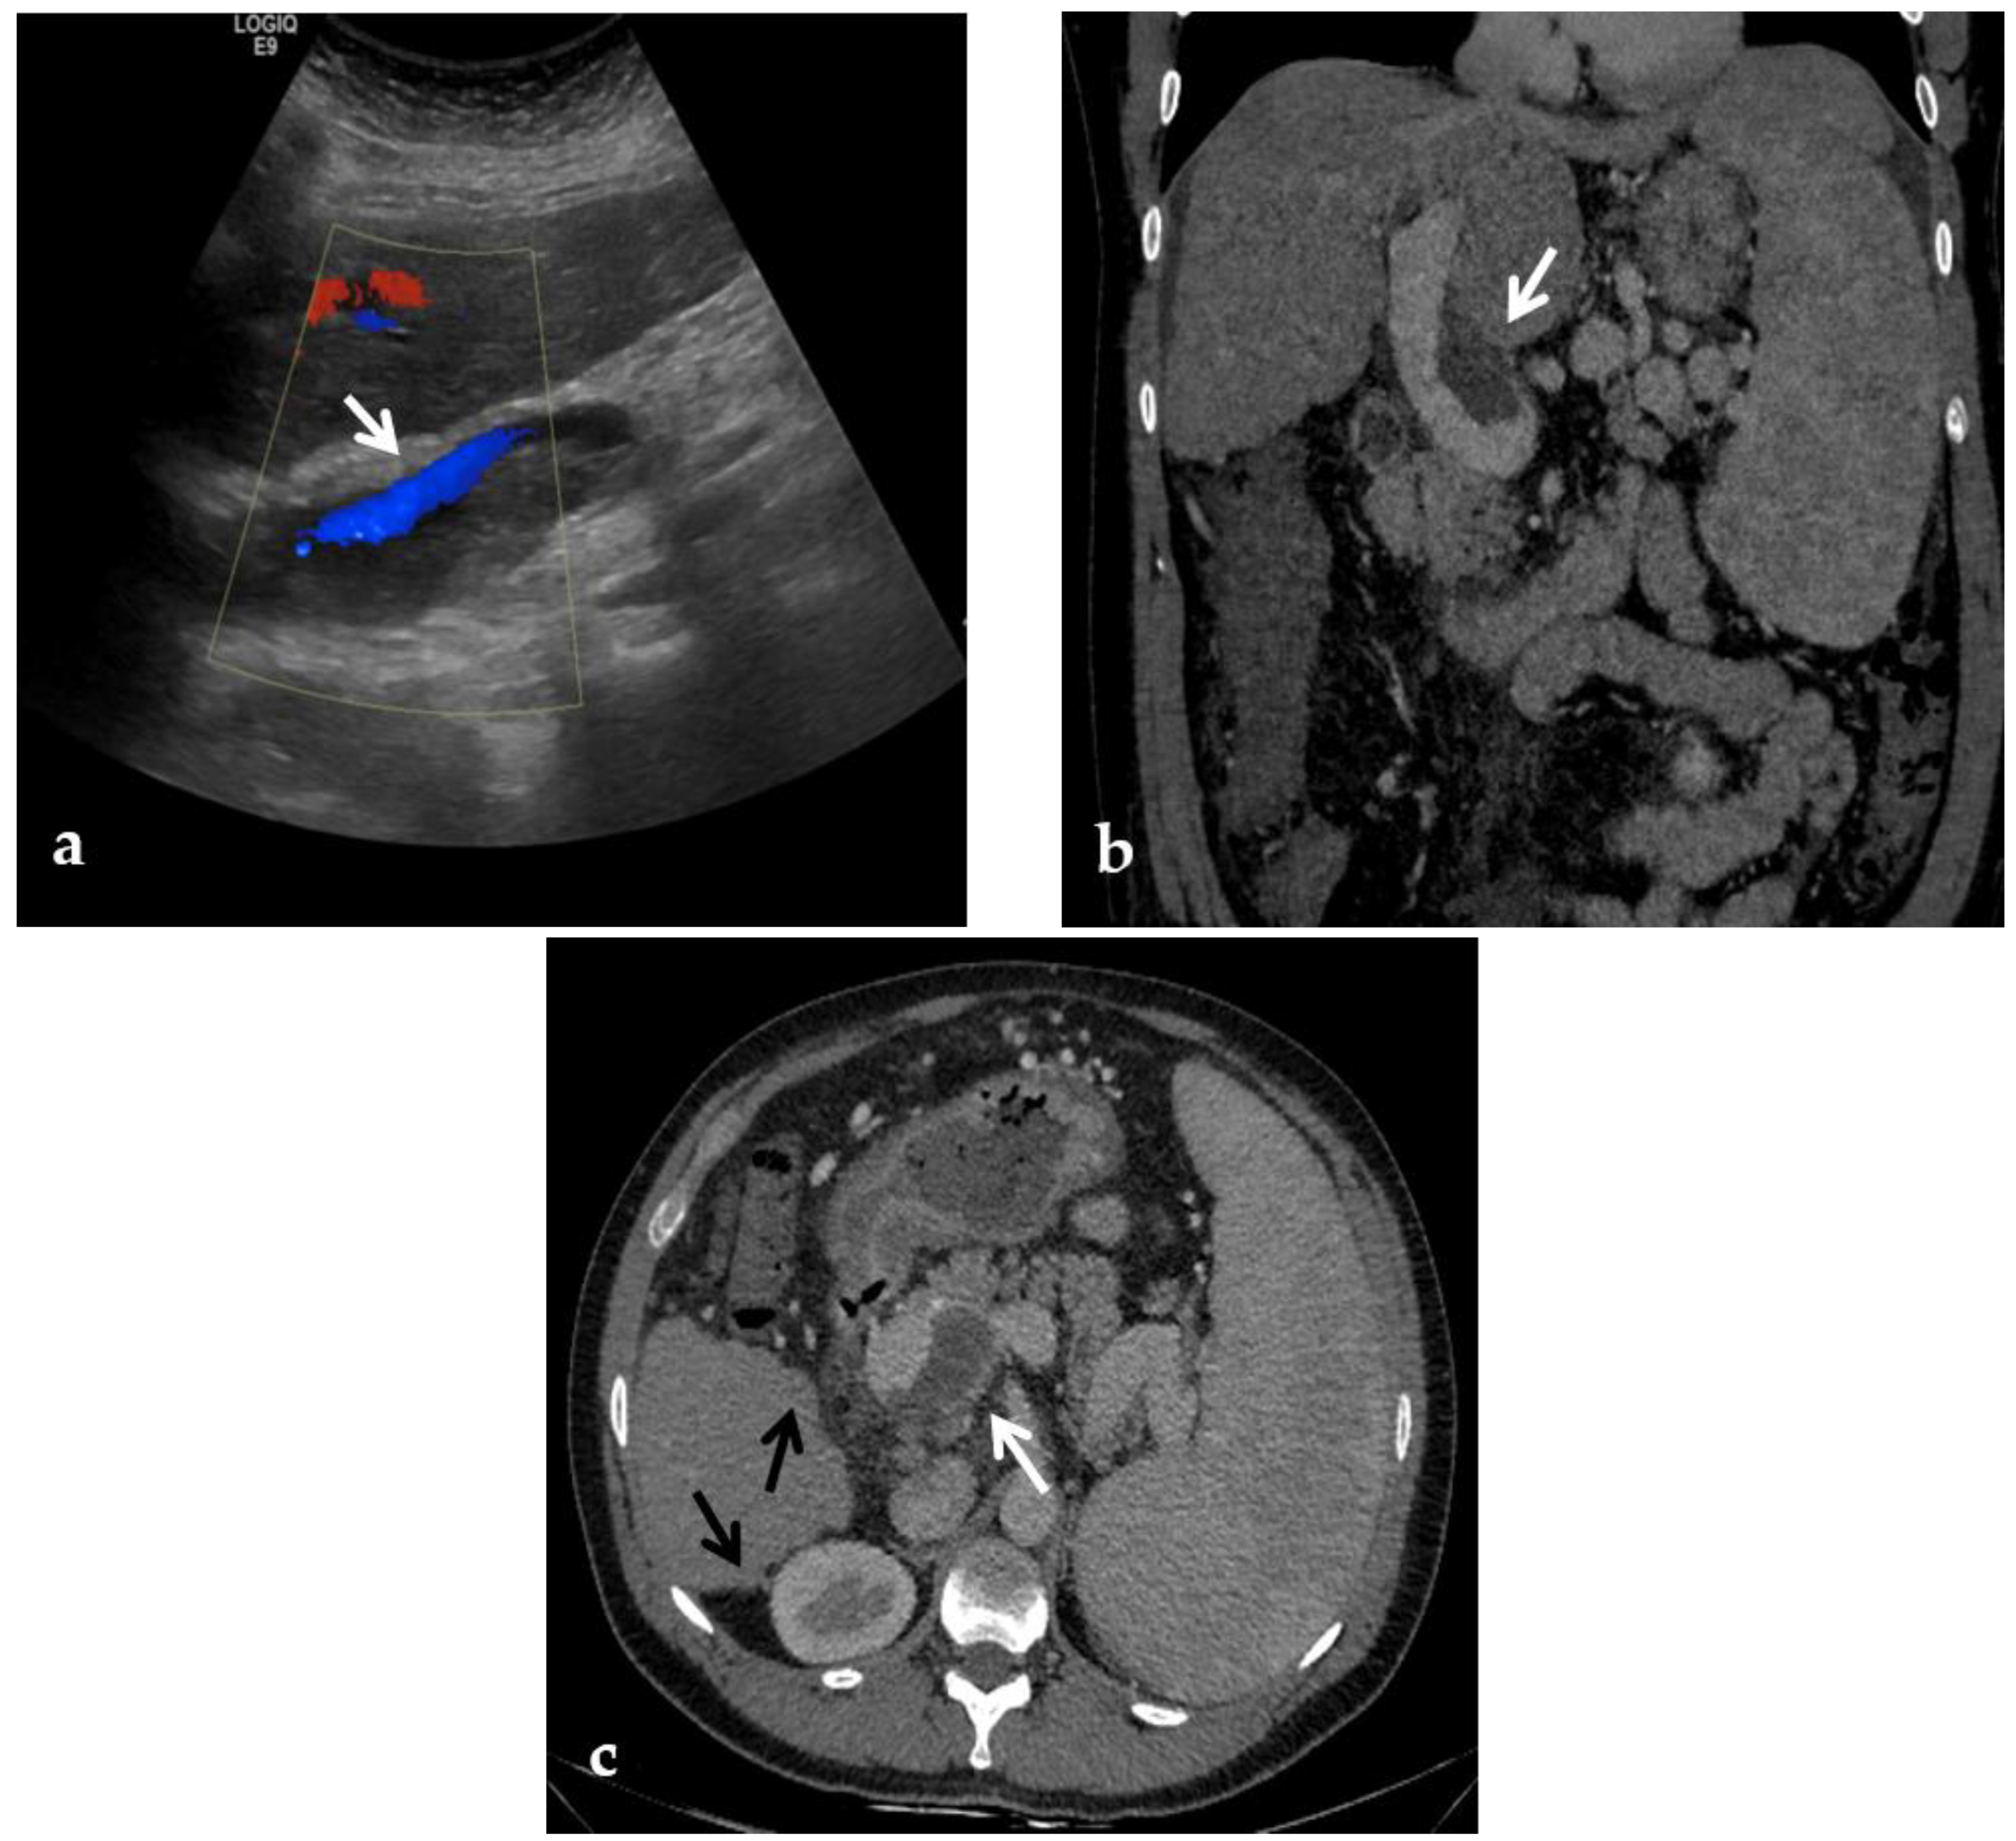

Stenosis and thrombosis of the bypass graft typically occur weeks to years after surgery and may be clinically evident with recurrence of portal hypertension and impaired liver function tests. Thrombosis or high-grade stenosis represents the main cause of bypass graft occlusion. CT may show a low-density cord, representing the occluded bypass. CDUS can show the thrombus with a hypoechoic appearance associated with an absence of portal flow. In these situations, stenosis and thrombosis can be treated with transhepatic, transsplenic, or transmesenteric portography and angioplasty. Balloon dilation can be performed when the transtenotic pressure gradient is greater than 5 mmHg or when a stenosis is radiologically confirmed [66] (Figure 14).

Figure 14.

Anteroposterior view of a percutaneous transsplenic portography imaging series of an occluded Meso-Rex bypass in the same patient of Figure 8. (a) Percutaneous transsplenic portography shows extensive jejunal and gastric varices (arrows), with no opacification of the Meso-Rex bypass. (b) After superior mesenteric vein catheterization, portography shows the portal cavernoma (arrow) with no opacification of the native intrahepatic portal branches (whose patency was documented with retrograde portography in Figure 8). (c) Portography image shows successful recanalization of the mesenteric anastomosis of the Meso-Rex bypass (white arrow), with intrahepatic portal branches opacification (black arrows). (d) X-Ray image shows angioplasty of the bypass performed through a 9-mm non-compliant balloon catheter. During angioplasty, a focal notch (arrow) representing the mesenteric anastomotic stenosis is clearly visible. (e) Portography image acquired after bypass recanalization and angioplasty shows regular opacification of the intrahepatic portal system (arrows). (f) Portography image from the superior mesenteric vein shows a re-expanded Meso-Rex bypass with complete opacification in the mesenteric anastomotic tract (arrow). The intrahepatic portal system is regularly represented; the portal cavernoma and gastro-jejunal varices disappeared.